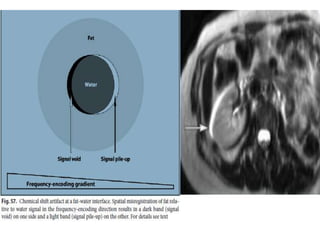

Chemical Shift

• cause

• occur on the basis of two mechanisms:

• 1, spatial mis-registration

• between fat and water (type 1) and

• 2, cancellation of the signal at the interface

between fat and

water (type 2)….on GE

remedy

• Use SE sequence

• Use fat suppression techniques

• Use wider reciever bandwidth

Chemical Shift  chemicalshift effects can be used to selectively suppress the signal from fat. • cause • occur on the basis of two mechanisms: • 1, spatial mis-registration • between fat and water (type 1) and • 2, cancellation of the signal at the interface between fat and water (type 2)….on GE

remedy • Use SEsequence • Use fat suppression techniques • Use wider reciever bandwidth Usage tissue characterization diagonsing fatty pathologies